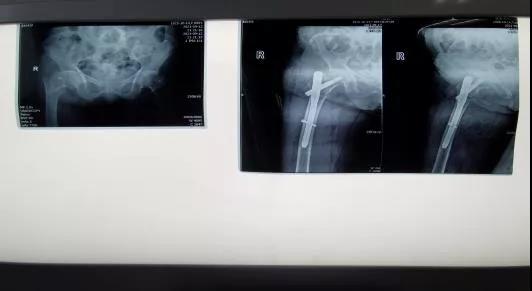

9月14日,在手术麻醉科副主任李万鹏、王永明医师和胡雪芳医师的配合下,实施“右侧股骨粗隆间骨折闭合复位髓内钉内固定术”,手术过程顺利。术后患者病情稳定,医疗组针对患者心肺功能、肾脏情况、营养等方面给予综合治疗;护理部对该患者进行护理查房,科室制定功能锻炼计划,由专职护士指导患者术后功能锻炼。